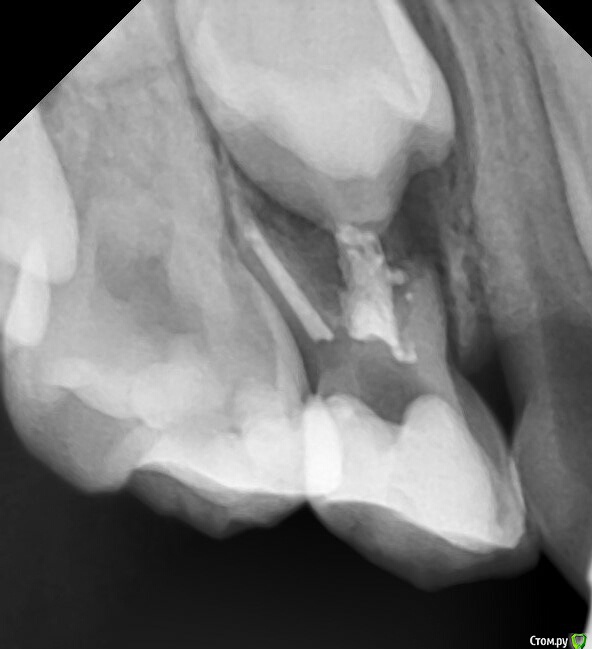

CRAZYDUCK Опубликовано 22 апреля, 2016 Поделиться Опубликовано 22 апреля, 2016 (изменено) 54 зуб ,в начале -лечение пульпита ампутацией ,через 1,5 года приехала со свищем в проекции щечного корня, без жалоб на это зуб ,сама увидела свищ .помыла гипохлоритом ,метапексом запломбировала ,килограмм метапекса из свища вышел.Через три месяца свища нет , но из канала ,в котором был свищ метапекс рассосался Надежнее удалять сомнительные ,с резорбцией ,большими очагами разрежения .это мое мнение Изменено 22 апреля, 2016 пользователем CRAZYDUCK 1 Ссылка на комментарий

crown Опубликовано 23 апреля, 2016 Автор Поделиться Опубликовано 23 апреля, 2016 2016-04-22 21.19.34.jpg54 зуб ,в начале -лечение пульпита ампутацией ,через 1,5 года приехала со свищем в проекции щечного корня, без жалоб на это зуб ,сама увидела свищ .помыла гипохлоритом ,метапексом запломбировала ,килограмм метапекса из свища вышел.2016-04-22 21.19.34.jpgЧерез три месяца свища нет , но из канала ,в котором был свищ метапекс рассосался 2016-04-22 21.19.00.jpgНадежнее удалять сомнительные ,с резорбцией ,большими очагами разрежения .это мое мнение я думаю причина в метапексе, он слишком быстро вымылся из разбитого апекса и опять резорбция, наверное в этой ситуации спас бы цинкэвгенольный цемент Ссылка на комментарий

CRAZYDUCK Опубликовано 23 апреля, 2016 Поделиться Опубликовано 23 апреля, 2016 (изменено) я думаю причина в метапексе, он слишком быстро вымылся из разбитого апекса и опять резорбция, наверное в этой ситуации спас бы цинкэвгенольный цементЯ останусь при своем ,просто этот зуб изначально подлежал удалению .Сегодня посетила семинар Елены Владимировна Небольсиной .Масса позитивных эмоций !настолько открытый ,позитивный и терпеливый человек .Елена приехала работать ! У нас был насыщенный день ,было 2 или 3 небольших 15 минутных перерывов. День полностью был посвящен обучению !Насчет ЦОЭ -в дентал фентэзи перестали им работать именно в каналах ,так как он ПРАКТИЧЕСКИ не рассасывается! Я не спросила название ,так как ЦОЭ (Эодент )просто стоит у меня без работы.но было очень много фото и рентген снимков ,подтверждающих, что рассасывание не происходило . Изменено 23 апреля, 2016 пользователем CRAZYDUCK 3 Ссылка на комментарий